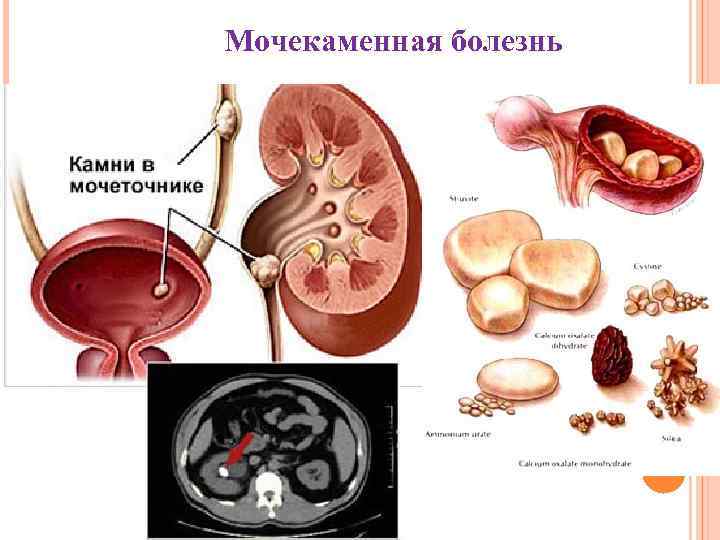

Мочекаменная болезнь

Мочекаменная болезнь